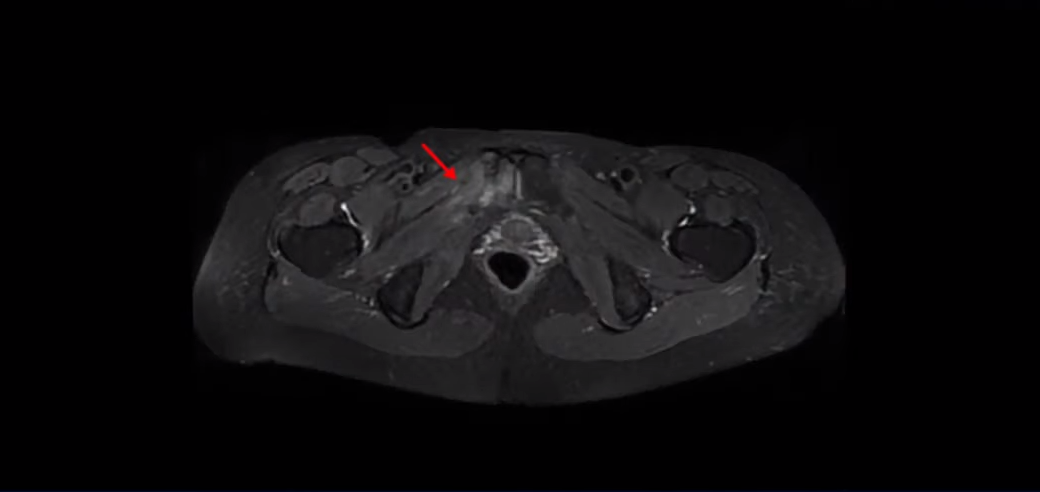

이 환자분은 아주 심하게 넘어지면서 엉덩이 근육이 파열되고 고관절에 미세 골절이 발생한 분입니다.

상태가 안 좋아 초음파를 했는데 엉덩이 근육이 심하게 파열돼 있고 인대도 많이 손상됐으며, Ct도 찍었는데 치골과 비구가 미세골절 상태였습니다. 정형외과 세 군데에서는 6개월 정도 아주 오래 걸리는 부위라고 무조건 집에만 있으라고 얘기했어요. 그리고 모든 선생님들이 염증이 지독하다 해서 소염진통제 3대를 맞았지만 전혀 나아지질 않고 열이 나면서 더 아파지고 쇠망치로 맞은 느낌과 화끈거림이 계속됐어요.